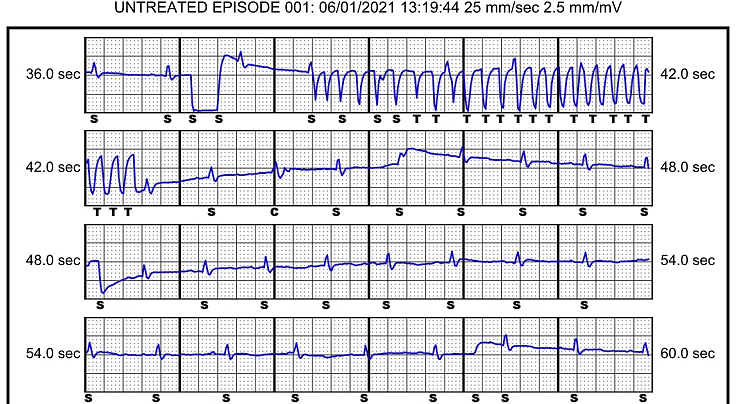

The following day a post implant check was performed. The check revealed multiple stored ‘untreated’ arrhythmia episodes. An example of an episode is displayed in figure 1. The check also revealed some baseline wander in the secondary and alternate sensing vectors, but not in the primary vector (figure 2). Device settings are displayed below.

Untreated S-ICD episode – an episode where tachycardia detection occurs, the device starts charging, but aborts the shock as the tachycardia rate confirmation algorithm criteria is not met, often because either the rhythm self-terminates or drops below the tachycardia detection rate

Figure 1 – Example 1 showing a subcutaneous ECG (S-ECG) untreated episode recording discovered at the post implant check. The sensing vector programmed is the secondary configuration.